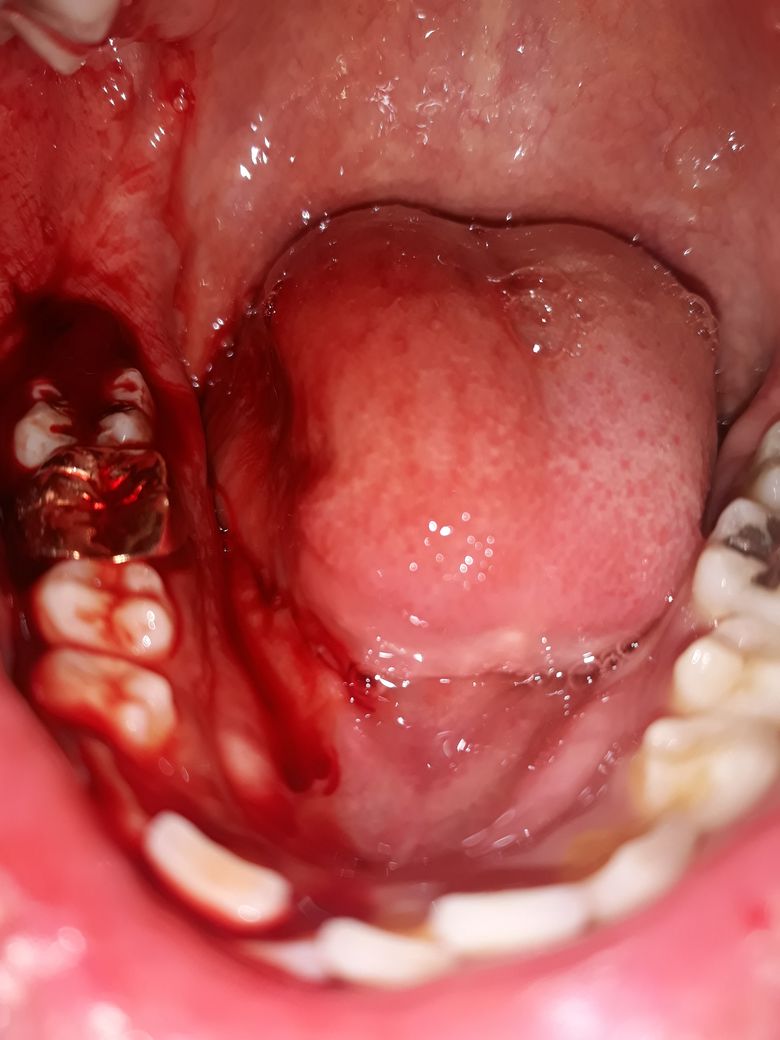

사랑니 발치 하고 이렇게 되면 병원 다시 가야하나요?

사랑니 발치하고

거즈 꽉물고 3시간 있다 뻊는데

피가 잘 안멈춰요 ㅜㅜ

이렇게 됬는데 병원 다시 가야겠죠?

• 1번 째 사진